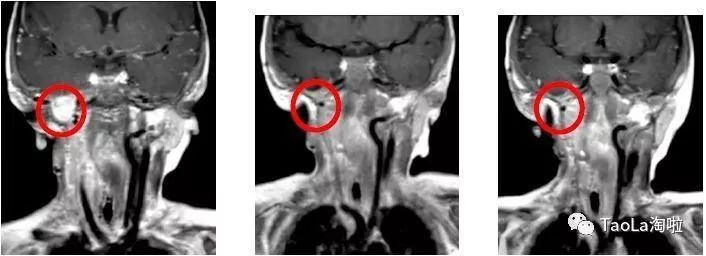

美国看病儿童纤维肉瘤:

16个月大的的婴儿

治疗前:经过基因检测后发现ETV6-NTRK3突变,出国看病服务机构了解到接受了3次手术和化疗,效果依然不明显。

治疗后:接受抗癌药Vitrakvi成人剂量的液体制剂治疗3周期后,MRI磁共振显示肿瘤体积减少90%!